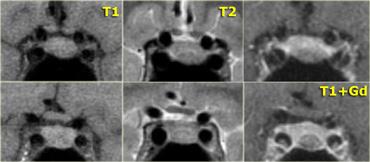

Hình ảnh chuỗi xung T1W và T2W mặt phẳng coronal, cùng với hình ảnh chuỗi xung T1W trước và sau tiêm gadolinium.

Ở bệnh nhân này, tổn thương trong tuyến yên chỉ có thể phát hiện được sau khi tiêm thuốc tương phản từ đường tĩnh mạch.

Chẩn đoán phân biệt: u tuyến yên vi thể hoặc nang khe Rathke.